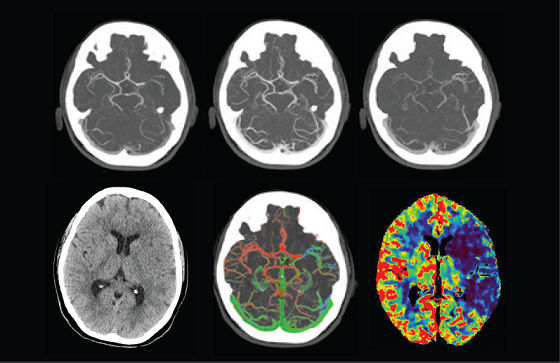

A patient with suspected TIA or stroke receives a general and neurological examination followed by diagnostic brain imaging, performed immediately on arrival so that treatment can be started promptly. 3 Optimal scanning coupled with workflow applications and protocols designed for stroke help deliver accurate and quick diagnosis to impact patient outcomes.

<p>FastStroke CT Application</p>

Read More

<p>Fast Brain protocol with HyperWorks</p>

Acute ischemic stroke is a complex disease and successful endovascular treatment is based on the comprehensive ability to rapidly integrate multiple pieces of information.4 Initiate Intravenous thrombolysis (IV-tPA) if less than 5 hours of ischemic stroke. Initiate mechanical thrombectomy within 6 hours of onset of large vessel stroke (MCA territory). Fast interventions with accurate imaging can help reach lesions quickly to help improve patient outcomes.